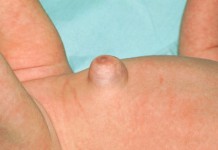

Пупочная грыжа

Что такое пупочная грыжа, ее причины, симптомы и методы лечения. Что такое пупочная грыжа? Пупочная грыжа характеризуется выпячиванием части кишечника, жировой ткани через слабое место в...